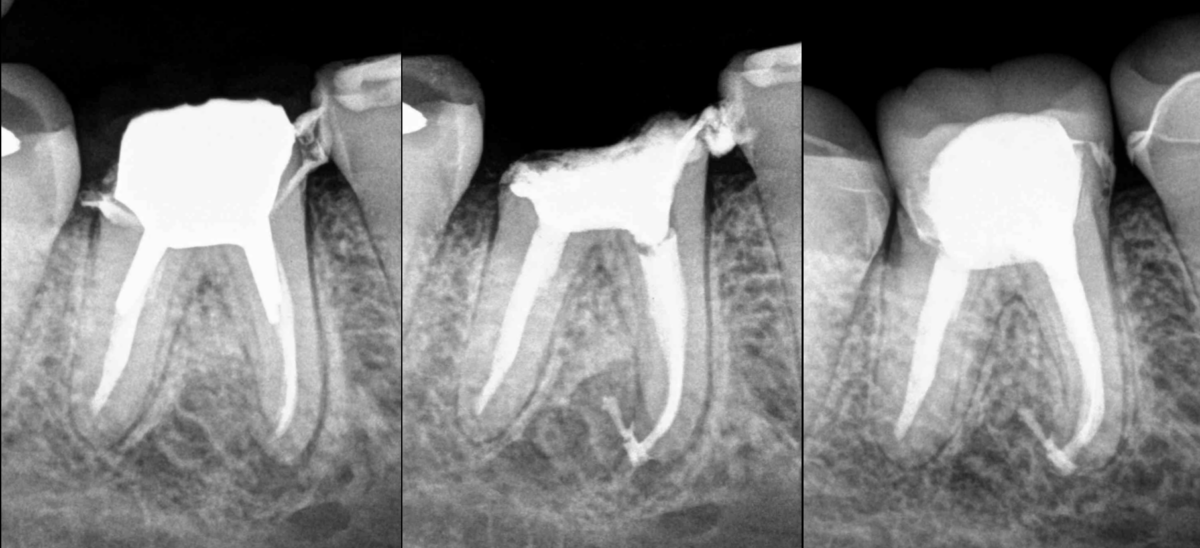

❓ Une fois le retraitement réalisé, que faire prothétiquement parlant ?

🔹 Un inlay-core (si celui-ci est indiqué bien sûr) ?

🔹 Un inlay-core + une couronne provisoire ?

🔹 Un inlay-core + la couronne finale ?

📊 Une fois le retraitement réalisé, nous avons entre 80 et 90% de chance que l’intervention soit efficace du point de vue de la cicatrisation osseuse.

✅ Si les racines sont accessibles à la microchirurgie endodontique (ce qui nous redonne 90% de chance de guérir les lésions osseuses), nous recommandons volontiers à nos correspondants la réalisation de l’𝐢𝐧𝐥𝐚𝐲–𝐜𝐨𝐫𝐞 (si celui-ci est indiqué) et de la 𝐩𝐫𝐨𝐭𝐡𝐞̀𝐬𝐞 𝐟𝐢𝐧𝐚𝐥𝐞.